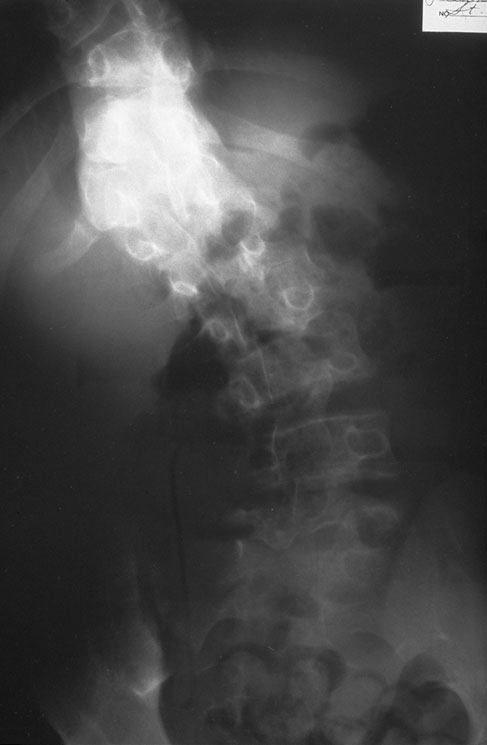

Curvature of the vertebral column is demonstrated here, typical for scoliosis.